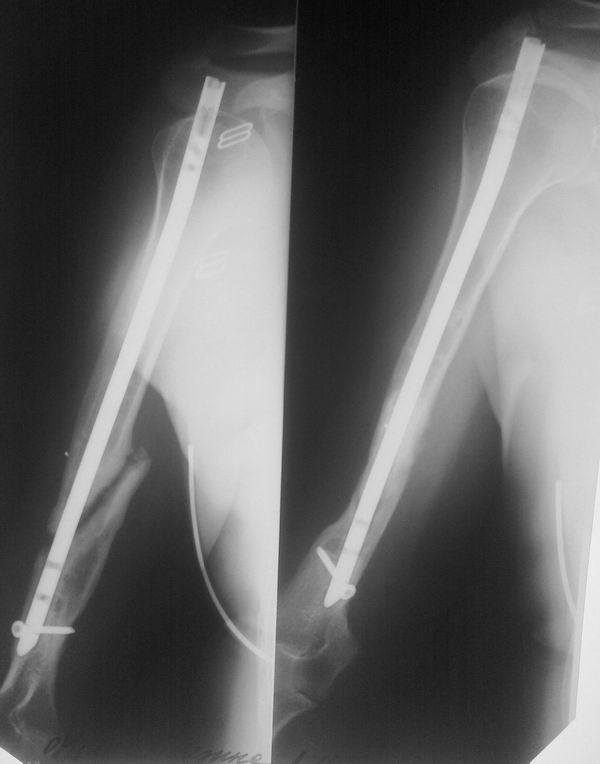

Уважаемые коллеги! Обратилась на консультацию пациентка 37 лет,

медицинский работник, с ложным суставом плечевой кости.

В 2010 г. получает закрытый оскольчатый перелом правого плеча. В одной

из больниц выполнен остеосинтез пластиной с угловой стабильностью. Через

год выявлена потеря стабильности фиксации, формирование ложного сустава.

В другой больнице удаляют пластину, выполняют остеосинтез стержнем.

Миграция проксимальных винтов, удаление их. в настоящее время вот такая

картина на Rg.

напрашивается удаление гвоздя и аппарат Илизарова.

Есть ли альтернатива, по вашему мнению?

В дистальном отломке "родного" канала, похоже нет. Стержень сформировал

"ложный ход".Интересуют возможность и  нюансы техники введения стержня в

таком случае.